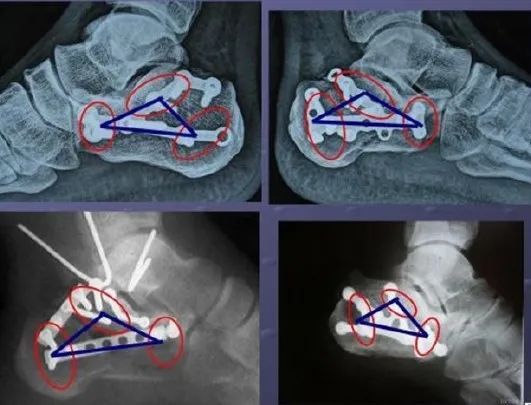

• 4)跟骨的Bohler"s角:缩小≥15°、消失或反角

• 5)跟骨的Gissan"s角:缩小≥90°或增大≥130°

技巧五、如何恢复跟骨的后关节面

牵引下骨刀根据距骨关节面,撬起协助恢复后关节面形态

一旦后关节面位置恢复,用2mm克氏针将较大的骨块钉在距骨上。维持复位的状态。

按照上述的1、2、3步(一牵二撬三穿)操作,即可完成跟骨高度、长度、后关节面的恢复。

Bohler“s角、Gissan”s角如果透视可显示正常。